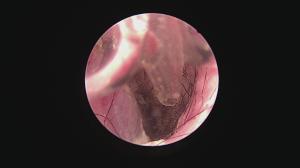

まずは処置前

鼓膜付近に耳垢がたまっております

ある程度鉗子で除去します

まだ鼓膜は確認できません。

鼓膜表面に汚れが付着しているのです。

まずは処置前

鼓膜付近に耳垢がたまっております

ある程度鉗子で除去します

まだ鼓膜は確認できません。

鼓膜表面に汚れが付着しているのです。